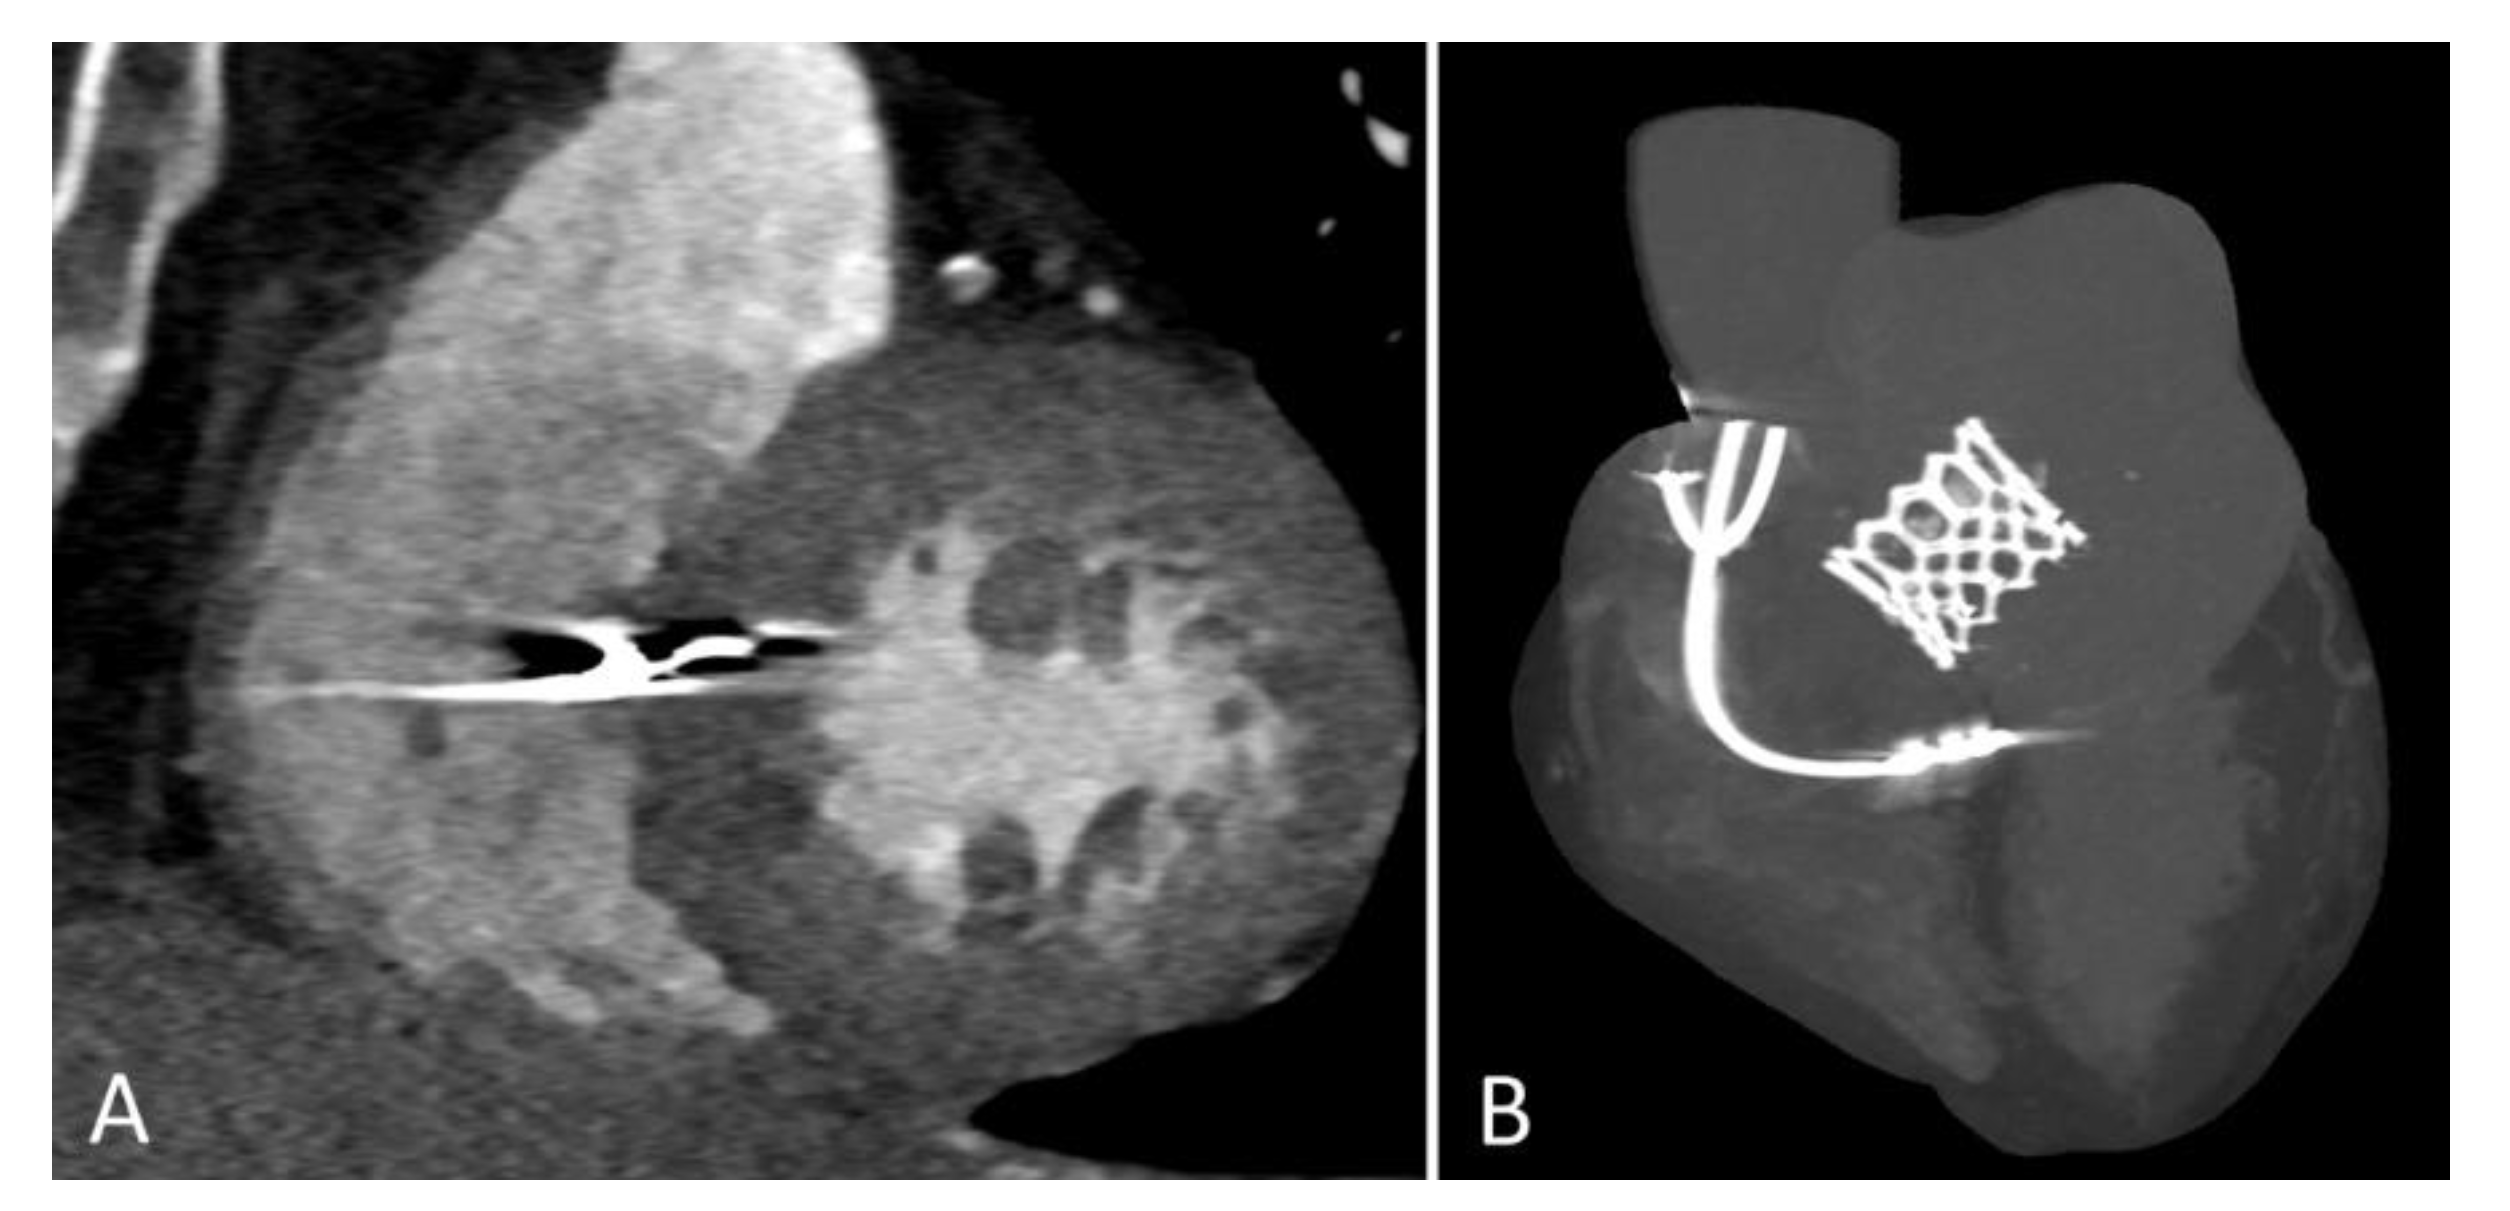

3.5. LBBAP Lead Implantation Technique